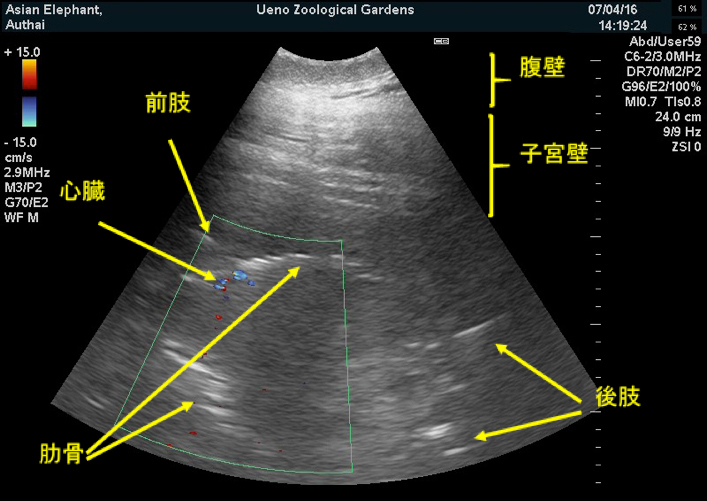

確実な判定のためには超音波検査(エコー検査)で胎児を確認しなければなりません。以来、定期的に超音波検査を実施してきたところ、2016年7月4日、胎児の体の一部と思われる画像が確認されました。また、その後の検査でも繰り返し確認できたため、妊娠確定と判断しました。

アジアゾウ「ウタイ」腹部超音波検査画像(2016年7月4日撮影)出産予定日